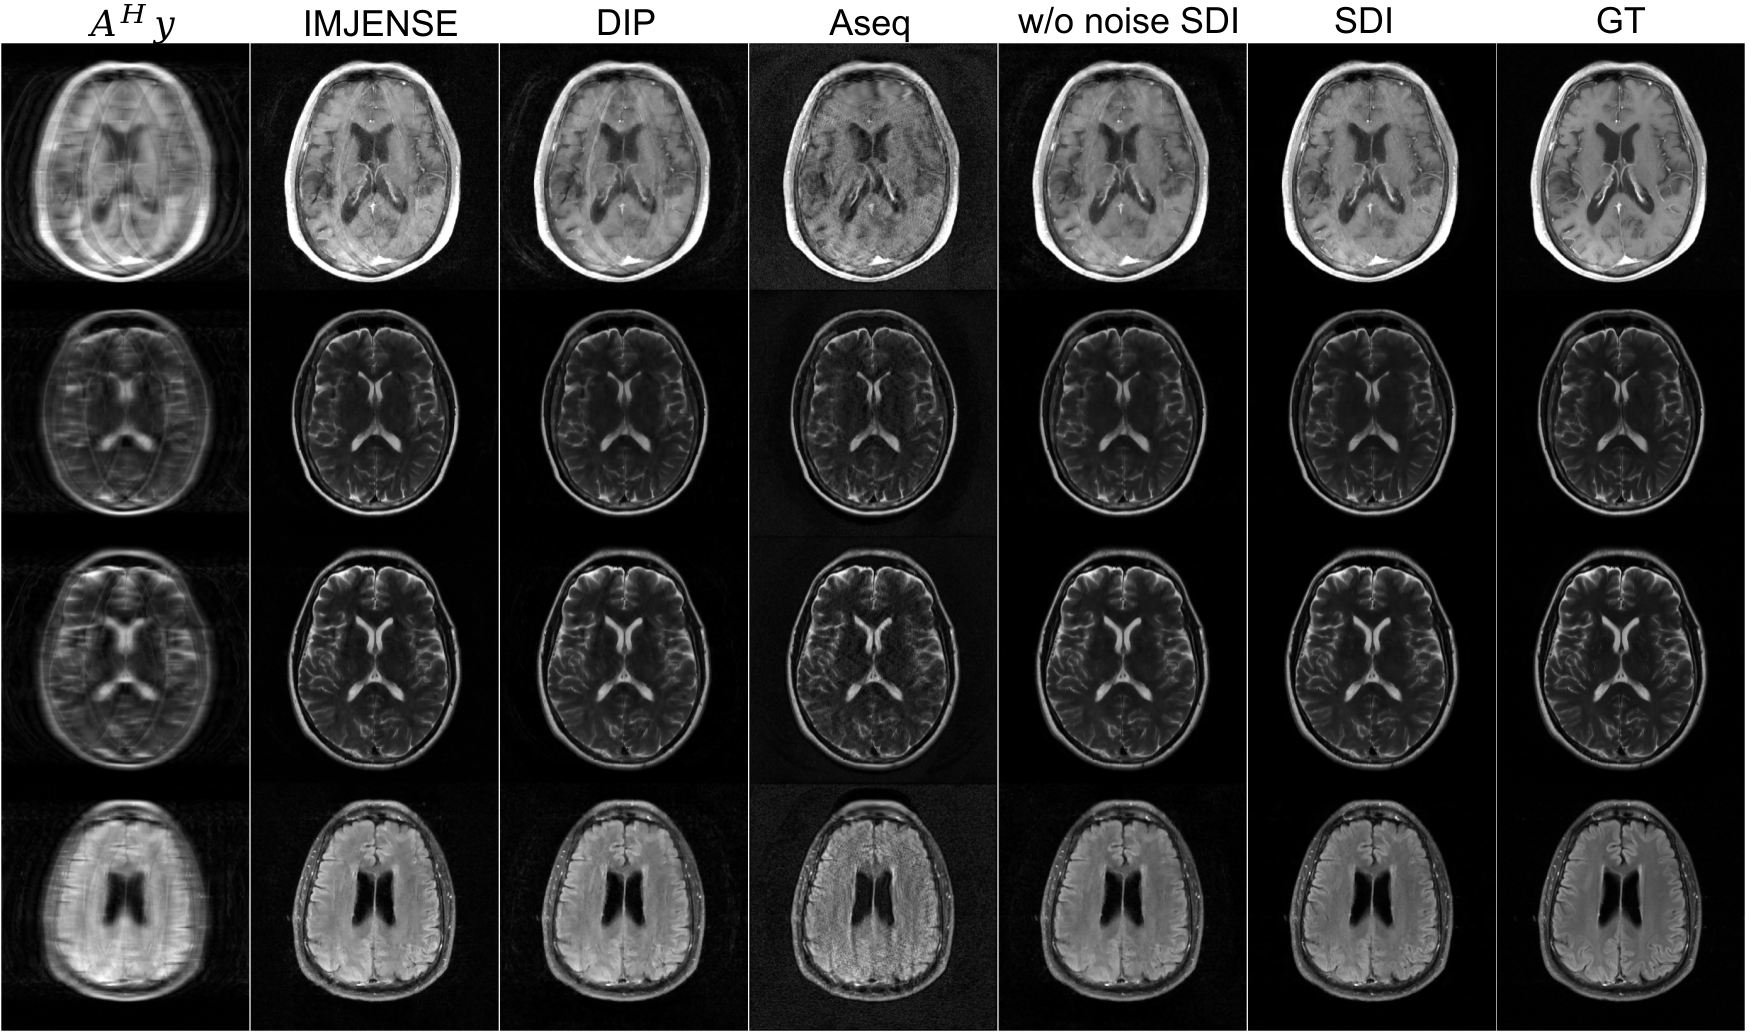

For self-diffusion, we initialize the 2D U-Net with Gaussian initialization {μ=0,σ=0.02}\{\mu=0,\sigma=0.02\} for convolutional kernels and zero initialization for biases. To ensure stable optimization and consistent data fidelity weighting, we normalize the k-space measurements before input to the reconstruction process. Specifically, we compute a scale factor to match the norm of the initialized network’s output to the norm of 𝒜H𝐲\mathcal{A}^{H}\mathbf{y}. The k-space measurements are scaled accordingly, preventing the network from unstable gradients due to mismatched signal energy. We use Adam optimizer in Algorithm˜1 and set parameters {T=40;K=50;η=0.001;βstart=1e3;βend=1e4}\{T=40;K=50;\eta=0.001;\beta_{\text{start}}=1e^{-3};\beta_{\text{end}}=1e^{-4}\}. We compare SDI to the following baseline methods: Aseq [23], IMJENSE [24], and Deep Image Prior (DIP). For these Aseq and IMJENSE, we use authors’s official implementations. The loss for DIP and SDI is enhanced with the total variation term, weight is set to 0.0001. As an ablation study, we also include SDI without resampling noise in Algorithm˜1 and refer it as “w/o ϵt\epsilon_{t} SDI”. The PSNR, SSIM, and NRMSE metrics are computed against the fully sampled ground truth. Table˜1 shows the reconstruction quality for all methods. SDI achieves the highest PSNR and SSIM, and the lowest NRMSE, outperforming Aseq and DIP that share the characteristic of using untrained networks but lack the iterative diffusion process. Figure˜4 compares the reconstructed images for 2D MRI from 4×\times undersampled k-space data without ACS lines. Visually, SDI reconstructs sharper anatomical boundaries and finer textures with fewer aliasing artifacts compared to other baselines. In Appendix˜E, Figures˜10 and 11 illustrate the visual results for 4×\times and 6×\times undersampled k-space data, respectively, and Figure˜8 reveals the evolution of the estimate over the self-denoising process.

Figure 10: Reconstruction from 4×\times undersampled k-space with 20 ACS lines using different methods (𝒜H𝐲\mathcal{A}^{H}\mathbf{y},IMJENSE, DIP, Aseq, w/o noise SDI, SDI) and corresponding error maps are shown.

Figure 11: Reconstruction from 6×\times undersampled k-space with 20 ACS lines using different methods (IMJENSE, DIP, Aseq, w/o noise SDI, SDI).